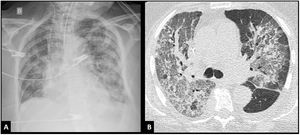

Conceptualmente, el síndrome de distrés respiratorio agudo (SDRA) consiste en un cuadro de insuficiencia respiratoria de comienzo agudo causada por edema pulmonar inflamatorio, caracterizado por el aumento de la permeabilidad vascular con extravasación de líquidos al intersticio alveolar y consecuente inundación de los espacios alveolares1. La pérdida de tejido pulmonar aireado exacerbada por la atelectasia de las zonas dependientes de la gravedad secundaria al incremento del peso del tejido pulmonar suprayacente, lleva al deterioro profundo de la oxigenación por aumento del shunt intrapulmonar y del espacio muerto alveolar; junto con una marcada disminución de la distensibilidad del sistema respiratorio. Esta situación fisiopatológica corresponde con la presencia de infiltrados pulmonares en la radiografía (Rx) y en la tomografía axial computarizada (TAC) de tórax (fig. 1 A y B). Desde el punto de vista anatomopatológico, la característica principal del SDRA es un patrón denominado daño alveolar difuso (DAD), que incluye la presencia de membranas hialinas, edema, necrosis de células alveolares tipo I y II, y hemorragia2,3. Esta descripción constituye el «modelo conceptual» del SDRA, y refleja como los clínicos «perciben» al síndrome4.

Imágenes de tóraxEl criterio imagenológico debe incluir infiltrados bilaterales en las Rx o TAC de tórax. Adicionalmente, en esta actualización se incorpora la ecografía pulmonar (evidencia de líneas B o consolidación (fig. 2 A y B). Cualquiera sea la modalidad empleada, debe sugerir pérdida de la aireación no totalmente explicada por colapso lobar, nódulos pulmonares o derrame pleural.